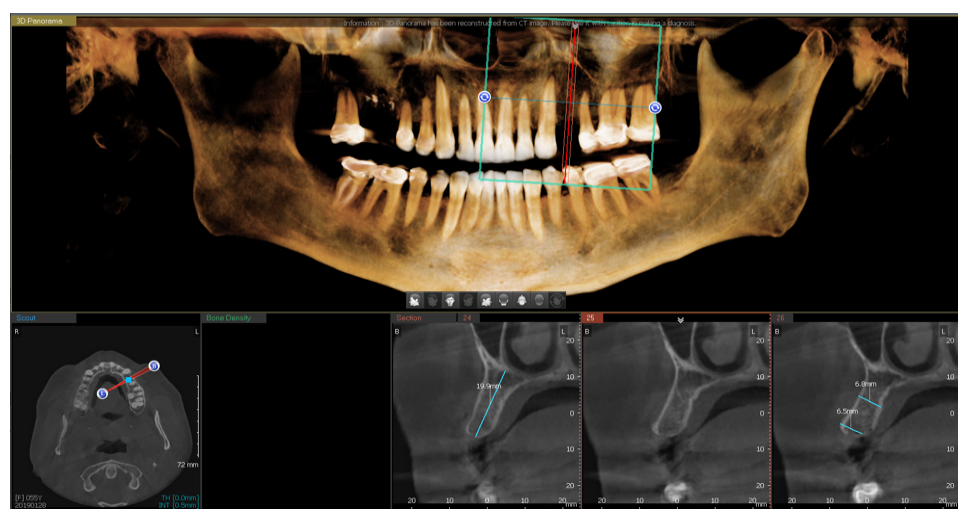

Un esame di secondo livello con TC Cone Beam (CBCT) è un tipo di procedura di imaging dentale che utilizza una tecnologia avanzata chiamata “Tomografia Computerizzata a Fascio Conico” o “Cone Beam Computed Tomography” (CBCT). Questo tipo di esame fornisce immagini tridimensionali ad alta risoluzione delle strutture interne.

La TC Cone Beam è una tecnica di imaging avanzata che fornisce una valutazione dettagliata ed è particolarmente utile in ambito odontoiatrico per la pianificazione implantare, per i trattamenti endodontici e più in generale per fare diagnosi in base alle varie problematiche.